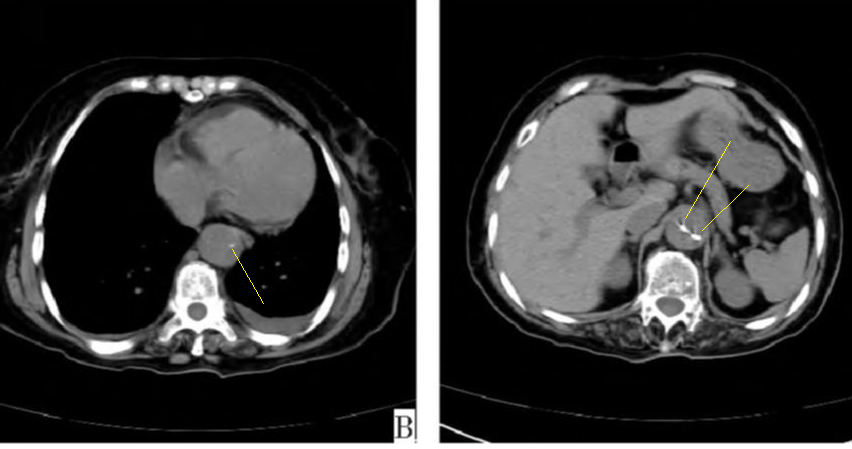

病例1

图3

病例2

下图的胸部CT平扫,有什么大问题?

图4

仔细一看,主动脉里面有线样高密度阴影!这个要高度警惕主动脉夹层!

图5

增强CT一看,吓到一大片!太惊悚了!

图6